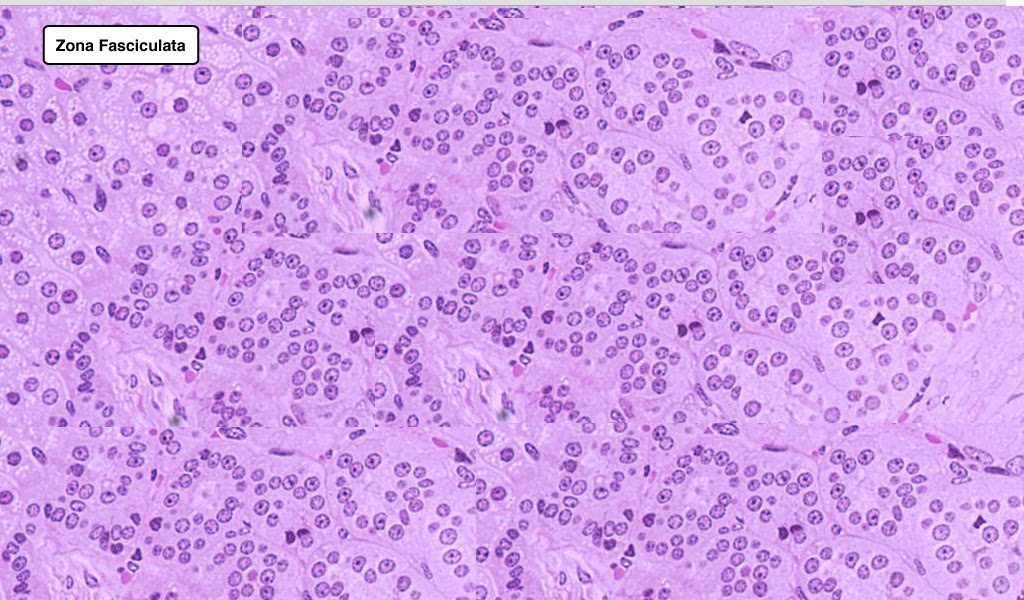

Human Adrenal Cortex Photograph by Jose Calvo / Science Photo Library

Human Adrenal Cortex Photograph by Jose Calvo / Science Photo Library Adrenal Cortex Anatomy The adrenal glands consist of an outer connective tissue capsule, a cortex and a medulla. Veins and lymphatics leave each gland via the hilum, but arteries and nerves enter. The adrenal glands, located superior to each kidney, consist of two regions: The adrenal gland consists of an outer cortex of glandular tissue and an inner medulla of nervous tissue. The. Adrenal Cortex Anatomy.